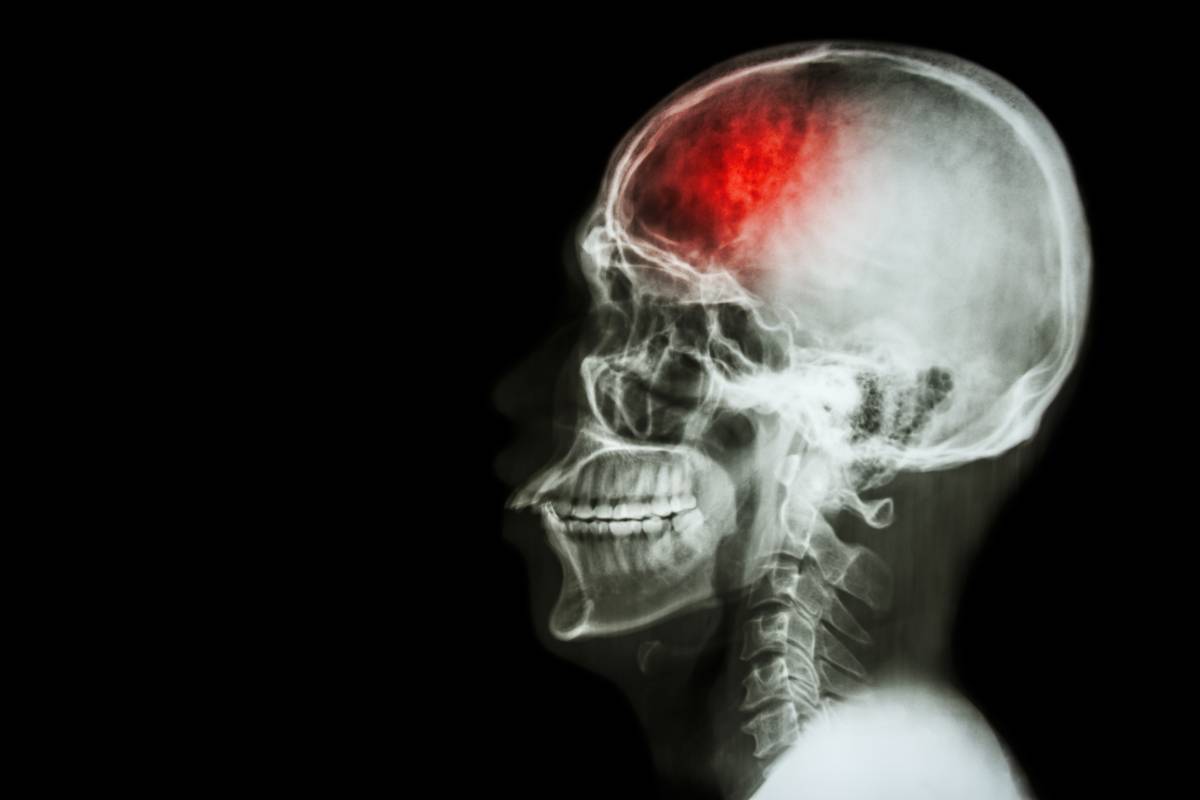

咱们中医讲的中风后遗症就是西医的脑卒中后遗症,其症状与《医林改错》原文中补阳还五汤的主治大致相同,不外乎是半身不遂,口眼歪斜,语言謇涩等,它作为一张祖传秘方,除了能治疗此病外,还可以治疗其他原因引起的偏瘫和截瘫,以及上肢或下肢痿软属气虚血瘀者,甚至对颈椎病造成的眩晕都有一定的疗效。